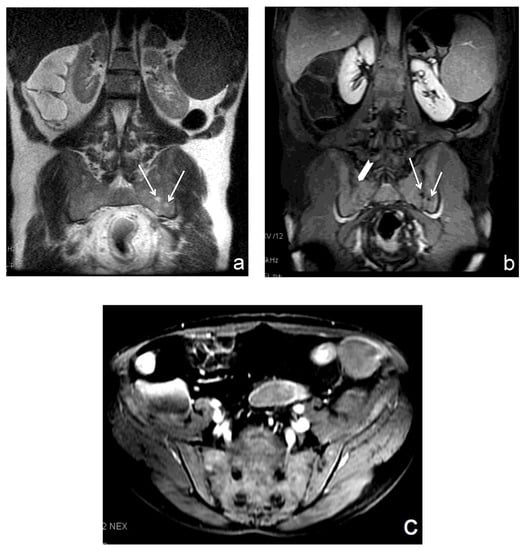

2.4. Image Evaluation

Figure 1. Subdivision of each sacroiliac joint (SIJ) into four quadrants according to a simplified SPARCC scoring system.